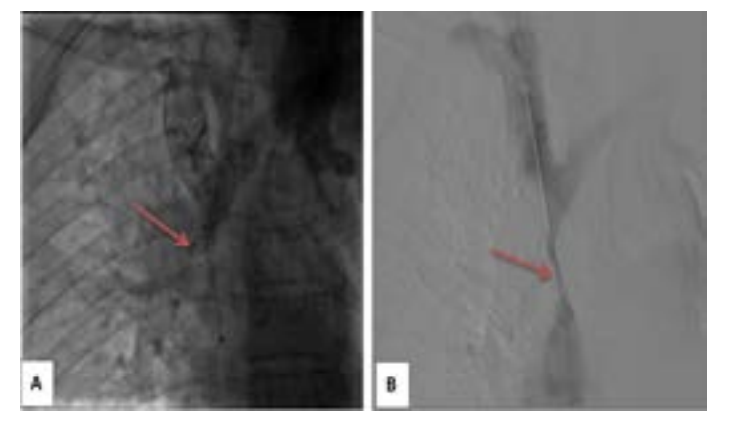

The venacavogram confirmed the absence of thrombus and revealed a stenosis in 3 cases and an occlusion in 2 cases. The stenosis/occlusion localization was the SVC in 3 cases and both SVC and the innominate venous trunk (IVT) in 2 cases.

From a therapeutic point of view, endovascular treatment of SVCS had been performed under local anesthesia. Percutaneous vena femoral approach was carried out in 2 cases. Three patients also required the use of the basilica pathway. Before stenting, the caval stenosis was dilated two or three times for almost 10 minutes by means of balloon inflation to the estimated diameter in three cases. We also routinely performed post-stent dilatation. In all procedures, a self-expanding stent had been deployed. The details regarding the stent deployed are summarized in Table 1. As an immediate follow-up, the patients experienced a quick relief of symptoms between 48-72 hours.